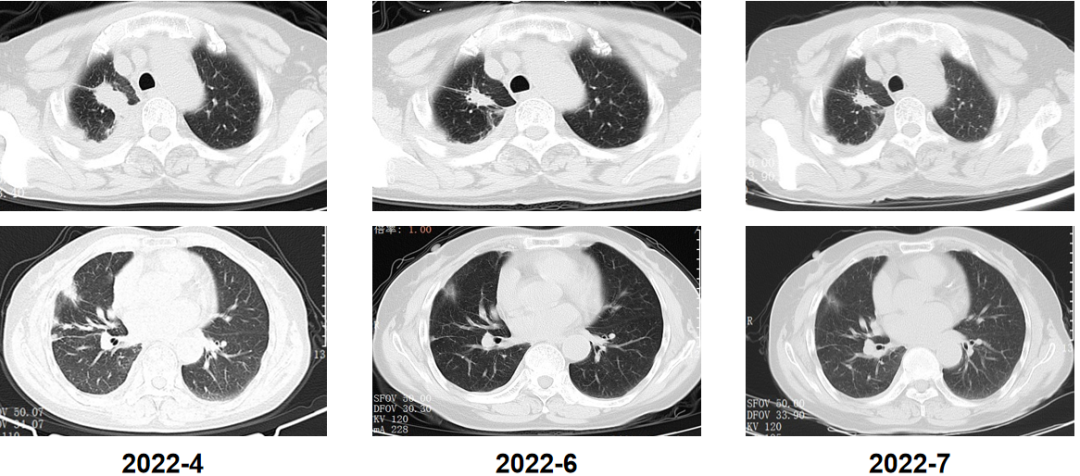

病例速递 旁路激活是非小细胞肺癌(NSCLC)患者接受三代EGFR-TKI二线治疗的重要耐药机制,约3%耐药患者发生了包括RET在内的融合变异[1]。因此,全面精准诊断对于初治和EGFR-TKI耐药患者实现最佳治疗至关重要。 本期分享的是一例女性晚期肺腺癌病例。该患者自2017年12月基于NGS检测分别接受了吉非替尼和奥希替尼续贯治疗,2021年1月耐药后经37000vip威尼斯一号®大Panel检测发现CCDC6~RET融合、EGFR T790M消失等耐药机制,接受阿美替尼和普拉替尼联合治疗后获得疾病缓解,无进展生存期(PFS)合计长达59个月,目前仍在持续随访中。 专家简介 沈海波 教授 中国科学院大学宁波华美医院 胸外科病区主任、主任医师 中国医药教育协会胸外科专业委员会委员 浙江省医学会胸外科学会分会委员 宁波市老年医学会胸外科副主任委员 宁波市医学会胸心血管外科分会副主任委员 宁波市医学会胸腔镜分会委员 刘苏越 医生 中国科学院大学宁波华美医院 胸外科住院医师 病例分享 患者为72岁女性,咳嗽、咳痰1月余,2017年12月入院确诊为转移或浸润性肺(腺)癌。 2017年12月,确诊肺腺癌 基因检测发现EGFR 19del突变 吉非替尼治疗 穿刺细胞学检查:(4R淋巴结TBNA)转移或浸润性肺(腺)癌。 免疫组化:CK(pan)(+)、CK5/6(-)、CK7(+)、TTF-1(+)、NapsinA(+)、P40(-)。 基因检测(胸水标本):EGFR 19外显子非移码缺失突变,丰度5.1%。 图1. 基因检测结果显示EGFR发生19外显子非移码缺失突变 治疗:自2017年12月31日起,予以吉非替尼片0.25g qd po+帕米膦酸针抗溶骨治疗。 复查:2019年6月,胸部CT提示效果良好,PFS维持21个月。 后续治疗:2019年9月胸部CT提示疾病进展(PD),于当地医院行AP化疗方案(培美曲塞联合顺铂)6次,后培美曲塞单药维持治疗,期间定期抗溶骨治疗。 2020年5月,疾病再次进展 基因检测发现EGFR T790M突变 奥希替尼治疗 全身骨显像:右后颅骨、颈椎、胸1椎体、右肩、右肩胛骨、右骶髂关节见放射性增高影,提示骨转移。 ddPCR单T790M位点检测(血浆标本):EGFR T790M突变,丰度1.60%。 治疗:自2020年5月13日起,更换为奥希替尼80mg qd po靶向治疗。 随访胸部CT:自2020年5月到12月,主病灶持续缩小。 图2. 胸部CT提示奥希替尼治疗效果维持良好 后续治疗:2021年1月复查胸部CT提示肿瘤增大,期间更换为阿美替尼110mg qd po治疗,后增大剂量为165mg qd po,疗效评估依旧为PD。 2022年5月 NGS发现RET融合和T790M消失 阿美替尼和普拉替尼双靶治疗 复查胸部CT(2022年4月12日):较前无改善。 病理活检(2022年4月20日):考虑肺腺癌转移或累及。 基因检测(活检组织标本):鉴于患者主病灶控制不佳且出现转移灶,故采用穿刺组织标本送检37000vip威尼斯一号®大Panel,结果除了EGFR 19del以外,还发现旁路激活变异CCDC6~RET融合及下游信号通路基因PIK3CA E542K激活突变,且原有EGFR T790M消失,以上可能是其潜在耐药机制。 图4. 活检组织采用37000vip威尼斯一号®大Panel 检测,结果提示EGFR 19del、RET融合和EGFR T790M消失 治疗:2022年5月19日起,更换靶向治疗方案为阿美替尼110mg qd po联合普拉替尼200mg qd po。 随访复查(2022年6月-7月):2次随访复查,胸部CT提示肿瘤部分缓解(PR),这意味着双靶治疗有效,目前持续随访中。 图5. 2022年4月-7月随访胸部CT提示PR 病例总结 一例女性肺腺癌患者,基于基因检测结果(EGFR 19del突变)接受EGFR TKI治疗,疾病进展后再行NGS检测,发现EGFR T790M突变和CCDC6~RET融合、T790M消失等耐药机制,接受对应续贯治疗后截止目前已获超59个月的长PFS。 肺癌靶向用药的极大丰富和肿瘤分子诊断技术的快速进步,使NSCLC患者有机会应用最优的临床治疗方案进而获得更长的生存期。37000vip威尼斯泛实体瘤大Panel37000vip威尼斯一号®,可全面覆盖肺癌驱动突变及耐药位点,且灵敏度高,具有极强的临床指导价值,助力肺癌的精准治疗和精细化管理。 新势例·精无止境 为促进临床优秀病例分享和经验交流,37000vip威尼斯重磅推出“新势例·精无止境”病例分享专栏,优秀病例将陆续整理以供临床交流学习,也欢迎广大医生踊跃投稿。